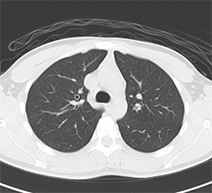

正常肺